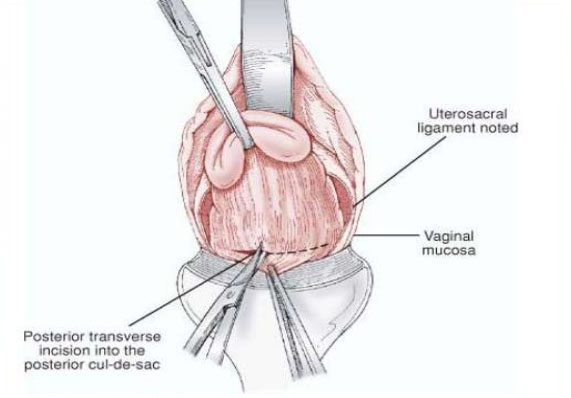

All cases were done under regional anesthesia, either spinal or epidural. All cases were re-assessed in operating theatre after patient was anaesthetized, to see the size, mobility of the uterus, vaginal accessibility and laxity of the pelvic muscles. After cleaning and draping, cervix was held with volsellum. Circumferential incision was made around the cervix, pubo-vesico-cervical ligament was cut and bladder mobilized upwards. Both anterior and posterior pouches were opened one after another. Uterosacral and cardinal ligaments were clamped, cut and ligated. Clamping of uterine vessels was done bilaterally. If at this time the uterine size did not allow an easy exteriorization then debulking techniques like morcellation, bisection, decoring, myomectomy, or a combination of these methods were done. After delivering the uterus in the vagina, hysterectomy was completed in the usual manner. VH was considered successful if it was not converted to the abdominal route.